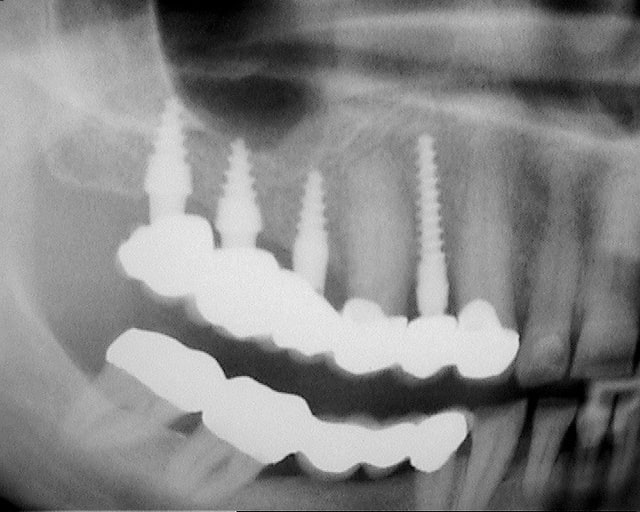

je voulais parler de ce fact pour les implants courts:minimum 4mm os vertical peut suffire (pour eviter un sinus lift externe de tatum) . dans ma pratique depuis quelques années je vois que ca marche , quelques cas cliniques des années passées.

j´ai oublié : 4mm plus 2mm( gagnés par un sinus lift interne)

C'est des implants Champions...

effectivement c'est bien ca mais ce n'est pas quelque chose d'uniquement possible avec ces implants i, ca doit etre possible également avec d'autres marques (comme l'a précisé cingullum) il est important que le bout ne soit pas trop agressif et si on veut passer en flapless condenser avec un extenseur pas trop agressif non plus.

Le plus important dans un implant sont les 4 premiers millimètres crestales ( c'est pourquoi de nombreuses industries, NB, astra,Bio horizon... ont chosit de faire des implants avec des micro fissures crestales pour augmenter la surface sur ces premiers millimètres et garantir une meilleure stabilité 1aire et 2aire).La partie dans l'os spongieux est moins décisive. Dans un contexte comme celui ci le platform switching est un facteur à ne pas négliger.